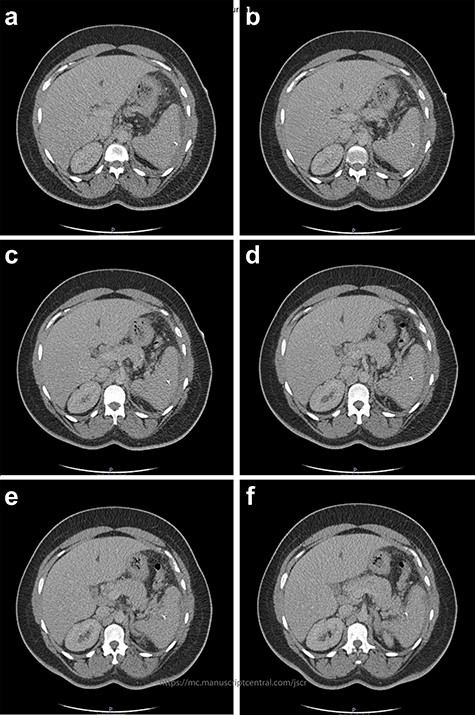

The patient remained clinically unwell and was considered for emergency splenectomy, with discussion in a multidisciplinary meeting. Fortunately, on Day 10 of treatment, a sustained decreased in inflammatory markers and resolution of the patient’s abdominal pain led to the multidisciplinary decision that the patient would be treated conservatively with intravenous antibiotics for 3 weeks. Once medically stable, the patient was placed on a further 3-week course of linezolid and booked for a follow-up outpatient CT with review in clinic. The scan showed resolution of the perisplenic collection, with the foreign body in situ (Fig. 5). The plan was to pre-vaccinate the patient in case of future emergency surgery; however, the patient did not attend the follow-up clinic appointments.

Two-mm axial section from the outpatient CT scan performed in November 2021, demonstrating resolution of the perisplenic haematoma with foreign body in situ.